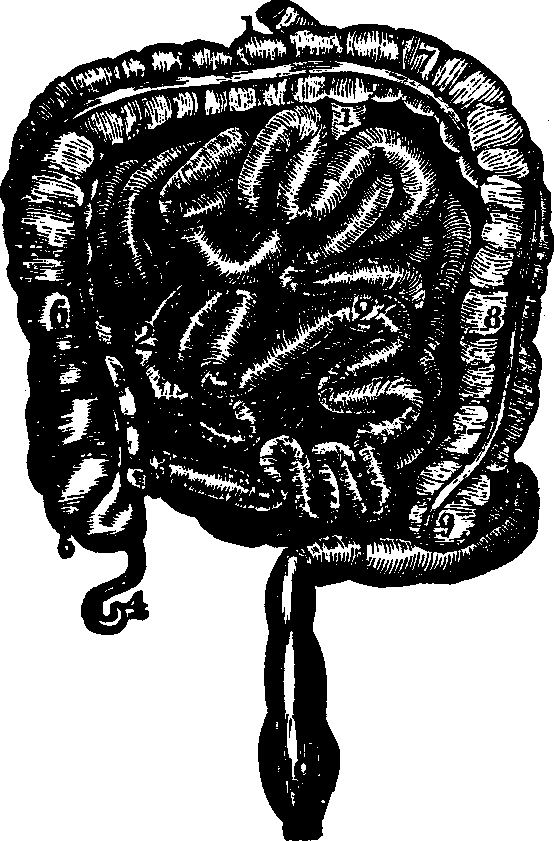

Fig. 29. Small and large intestines. 1, 1, 2, 2. Small intestine.

3. Its termination in the large intestine. 4. Appendix

vermiformis. 5. Cæcum. 6. Ascending colon. 7.

Transverse colon. 8. Descending colon. 9. Sigmoid flexure of

colon. 10. Rectum.

The Intestines are those convoluted portions of the alimentary canal into which the food is received after being partially digested, and in which the separation and absorption of the nutritive materials and the removal of the residue take place. The coats of the intestines are analogous to those of the stomach, and are, in fact, only extensions of them. For convenience of description, the intestines may be divided into the small and the large. The small intestine is from twenty to twenty-five feet in length, and consists of the Duodenum, Jejunum, and Ileum. The Duodenum, so called because its length is equal to the breadth of twelve fingers, is the first division of the small intestine. If the mucous membrane of the duodenum be examined, it will be found thrown into numerous folds, which are called valvulæ conniventes, the chief function of which appears to be to retard the course of the alimentary matter, and afford a larger surface for the accommodation of the absorbent vessels. Numerous villi, minute thread-like projections, will be [pg 41]found scattered over the surface of these folds, set side by side, like the pile of velvet. Each villus contains a net-work of blood-vessels, and a lacteal tube, into which the ducts from the liver and pancreas open, and pour their secretions to assist in the conversion of the chyme into chyle. The Jejunum, so named because it is usually found empty after death, is a continuation of the duodenum, and is that portion of the alimentary canal in which the absorption of nutritive matter is chiefly effected. The Ileum, which signifies something rolled up, is the longest division of the small intestine. Although somewhat thinner in texture than the jejunum, yet the difference is scarcely perceptible. The large intestine is about five feet in length, and is divided into the Cæcum, Colon, and Rectum. The Cæcum is about three inches in length. Between the large and the small intestine is a valve, which prevents the return of excrementitious matter that has passed into the large intestine. There is attached to the cæcum an appendage about the size of a goose-quill, and three inches in length, termed the appendix vermiformis. The Colon is that part of the large intestine which extends from the cæcum to the rectum, and which is divided into three parts, distinguished as the ascending, the transverse, and the descending.